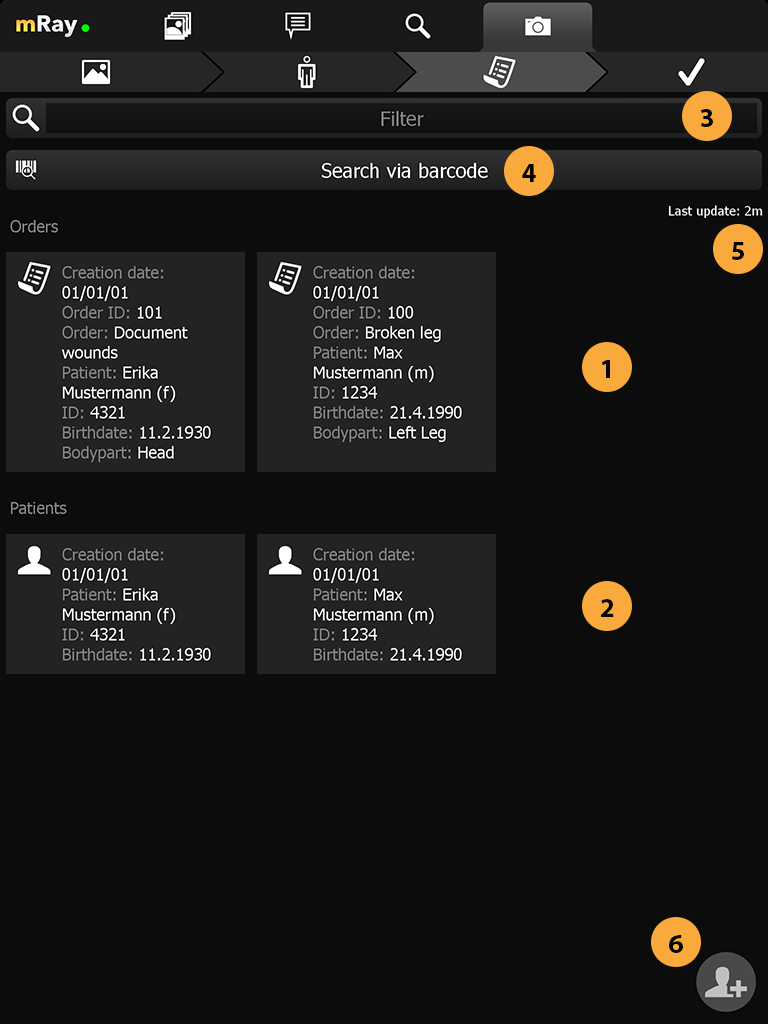

Wechseln zur Fotodokumentation

Fotofunktion aufrufen: Siehe Abschnitt Fotodokumentation zur näheren Erläuterung.